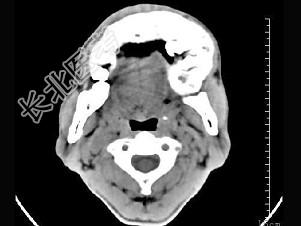

- 单项选择题女,23岁, 左颌部疼痛肿胀一年余,近来加重, CT表现如图,最可能的诊断是 ( )

A、造釉细胞瘤

B、混合性牙瘤

C、中央性颌骨癌

D、颌骨血管瘤

E、牙龈癌